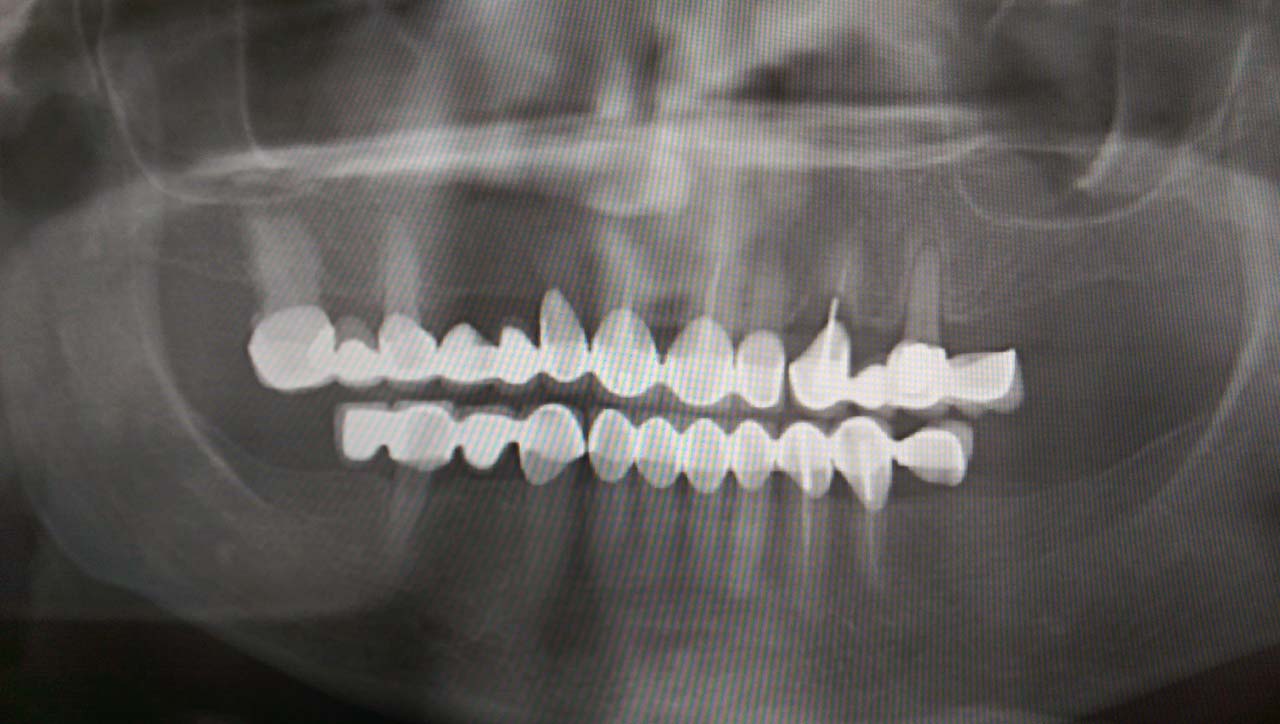

Elhanyagolt fogsor cseréje 2 nap alatt

2 nap alatt varázsoltuk ezt a szép esztétikus alsó, felső körhídat implantátumokkal megtámasztva a korábban elhanyagolt szájba. Az 1. nap 26 fogat távolítottunk el, mert annyira rossz állapotban voltak, és rögtön azonnal terhelhető IHDE svájci implantátumokat raktunk be, fentre 8, lentre 6 darabot. A sebeket összevarrtuk és intraorális szkennerrel digitális lenyomatot vettünk. 2 nap múlva pedig beragasztottuk a kész PMMA műanyag körhidakat. Dr. Kelemen Péter és a Symbion Fogtechnika munkája.